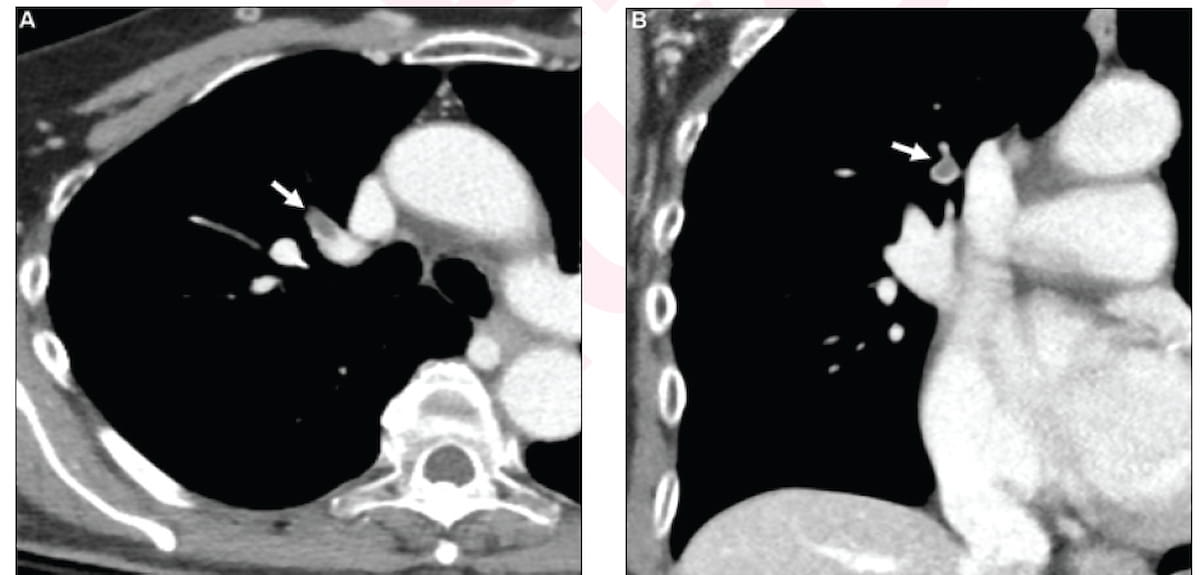

Here one can see contrast-enhanced CT images for a 71-year-old woman diagnosed with incidental pulmonary embolism (IPE). New research suggests a significantly higher one-year mortality risk for women diagnosed with pulmonary embolism (PE) than men. (Images courtesy of the American Journal of Roentgenology.)